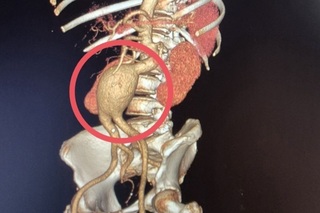

Как пояснили медики, к ним поступила 60-летняя пациентка с крайне опасным диагнозом — мешотчатая аневризма брюшной аорты.

«Это патологическое расширение главного сосуда организма, которое в любой момент может привести к внутреннему кровотечению. Случай действительно уникальный — аневризма брюшной аорты считается «бомбой замедленного действия», а мешотчатая форма особенно опасна из-за риска мгновенного разрыва.

Операцией руководил заведующий отделением сосудистой хирургии БГКБ Андрей Ковалев, она продлилась более шести часов и прошла успешно. Угроза жизни отступила.